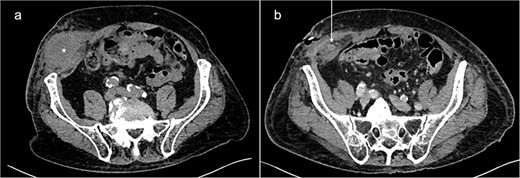

An 87-year-old male on oral anticoagulant therapy was admitted to the emergency department with abdominal pain for 1 week. On physical examination, a painful mass could be palpated in the right lower quadrant of the abdomen, accompanied by local signs of inflammation. Blood tests revealed elevated levels of C-reactive protein (CRP) and white blood cells (WBC). The patient had no history of previous surgery in the lower abdomen. A computed tomography (CT) scan showed a large fluid collection in the abdominal wall, primarily interpreted as a superinfected hematoma (Fig. 1). Incision and drainage of the collection was performed, which released large quantities of pus. Consequently, the patient was put on broad-spectrum antibiotics.

Abdominal CT-scans on initial presentation (a) and day 5 (b). A large fluid collection (*) can be seen in the right lower abdominal wall. After drainage, the appendix (white arrow) could be identified inside the abscess cavity, indicating the existence of a PVH.

During the following days, purulent discharge from the wound continued and the patient developed signs of sepsis. Abdominal CT was repeated, which now revealed acute appendicitis inside an atypical PVH in the right peri-inguinal region (Fig. 1). Thus, the patient was taken back to the operating room for laparoscopy and abdominal wall exploration. Intraoperatively, a segment of terminal ileum and the appendix were found trapped inside the hernia orifice (Fig. 2). After reduction of the herniated contents, laparoscopic appendectomy was performed uneventfully. The remaining abscess cavity was generously incised, debrided and left open to facilitate secondary wound closure (Fig. 3). This was eventually achieved using a vacuum-assisted closure (VAC) device and secondary suture. After management of concomitant medical conditions, the patient was discharged from the hospital on the 11th postoperative day. No physical follow-up was conducted as the patient declined further surgery for hernia repair due to poor general condition.